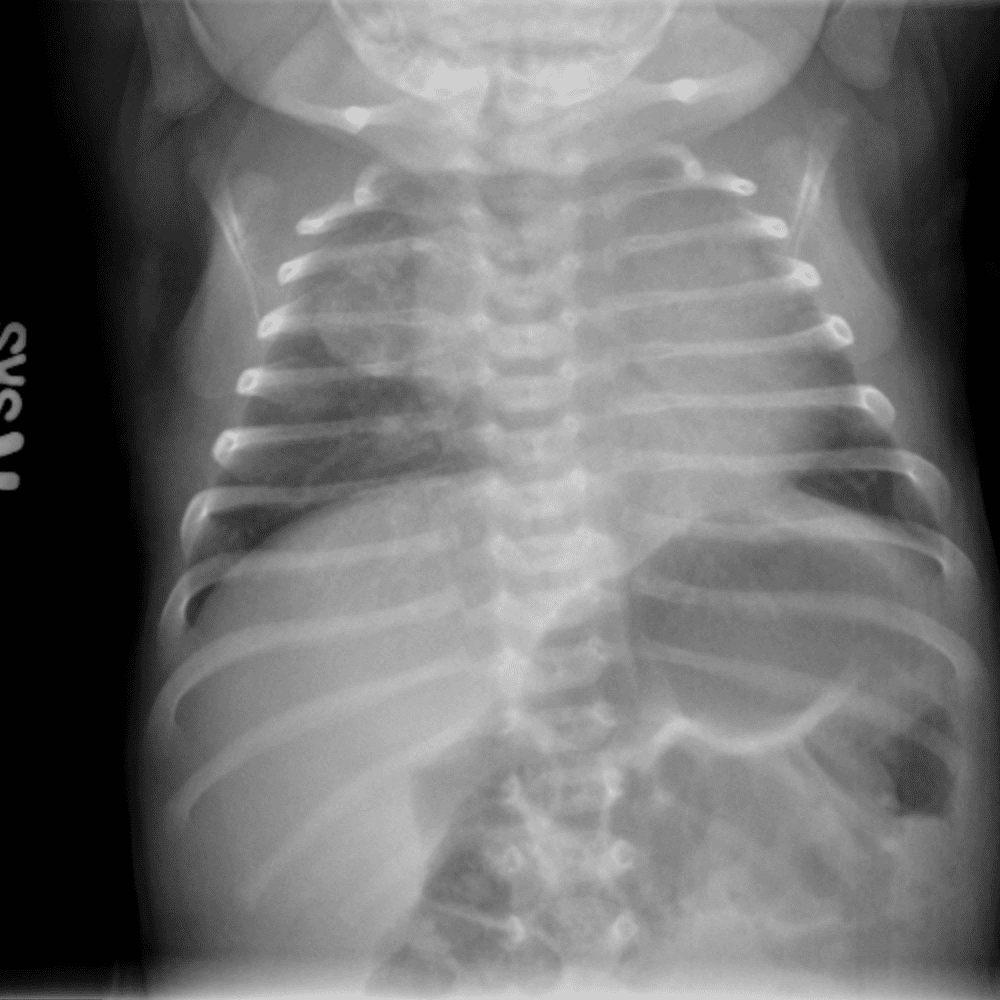

Peds Chest

Practice

Simulates call by including subtle or difficult cases and some normals.

50 cases